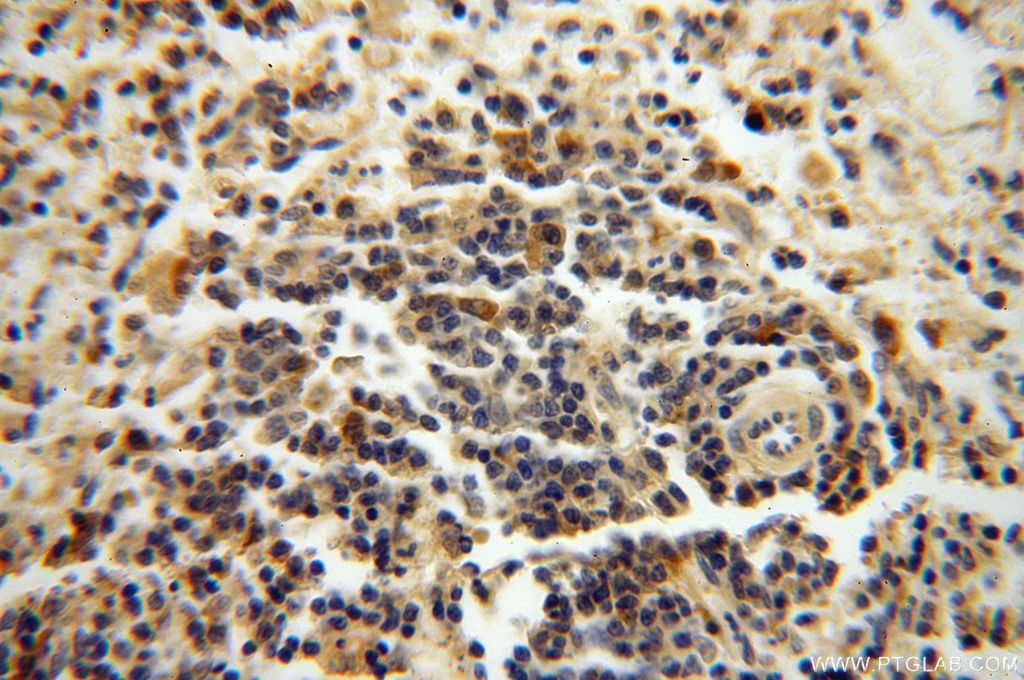

| Positive IHC detected in | mouse testis tissue, human heart tissue, human kidney tissue, human placenta tissue, human testis tissue, human skin tissue, human brain tissue, human spleen tissue, human lung tissue, human ovary tissue, rat spleen tissue Note: suggested antigen retrieval with TE buffer pH 9.0; (*) Alternatively, antigen retrieval may be performed with citrate buffer pH 6.0 |

| Immunohistochemistry (IHC) | IHC : 1:50-1:500 |